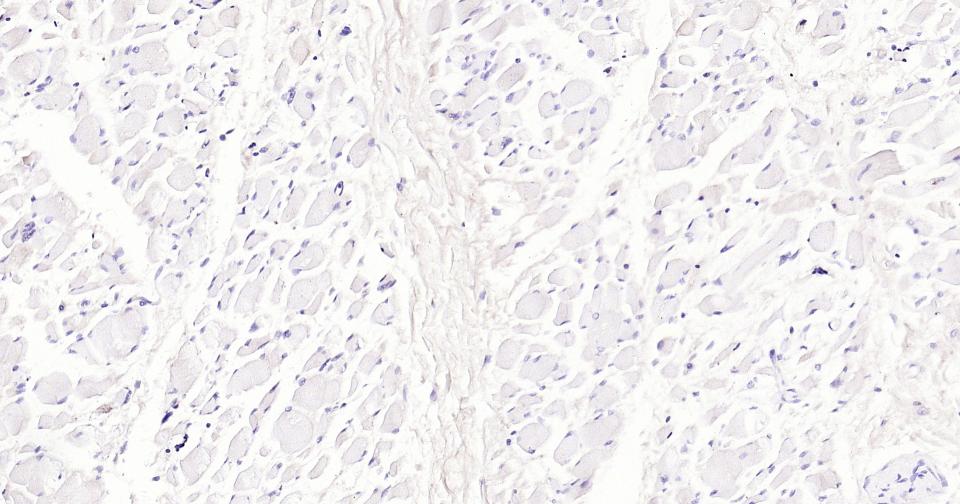

(Negative control)Paraformaldehyde-fixed, paraffin embedded Rat Skeletal muscle; Antigen retrieval by boiling in sodium citrate buffer (pH6.0) for 15 min; Antibody incubation with LRP2 Monoclonal Antibody, Unconjugated(bsm-42103R) at 1:200 overnight at 4°C, followed by conjugation to the SP Kit (Rabbit, SP-0023)and DAB (C-0010) staining.

(Negative control)Paraformaldehyde-fixed, paraffin embedded Mouse Skeletal muscle; Antigen retrieval by boiling in sodium citrate buffer (pH6.0) for 15 min; Antibody incubation with LRP2 Monoclonal Antibody, Unconjugated(bsm-42103R) at 1:200 overnight at 4°C, followed by conjugation to the SP Kit (Rabbit, SP-0023)and DAB (C-0010) staining.

(Negative control)Paraformaldehyde-fixed, paraffin embedded Human Skeletal muscle; Antigen retrieval by boiling in sodium citrate buffer (pH6.0) for 15 min; Antibody incubation with LRP2 Monoclonal Antibody, Unconjugated(bsm-42103R) at 1:200 overnight at 4°C, followed by conjugation to the SP Kit (Rabbit, SP-0023)and DAB (C-0010) staining.